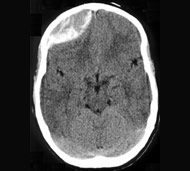

Епідуральна гематома

Цю гематому також називають екстрадуральною, вона розвивається при розриві кровоносної судини - зазвичай артерії - між зовнішньою поверхнею твердої мозкової оболонки і черепом. Часто пошкодження кровоносної судини відбувається внаслідок перелому черепа. Кров витікає між твердою мозковою оболонкою і черепом, утворює масу, яка здавлює тканини головного мозку.

Ризик смерті від епідуральної гематоми є значним, якщо швидко не почати лікування. Деякі пацієнти з подібним видом травми можуть залишатися у свідомості, але більшість перебувають у сонному або коматозному стані з моменту отримання травми.

Епідуральні гематоми більш поширені у дітей та підлітків. Найчастіше вони є результатом авто- чи мотоаварії та інших травматичних подій.

Діагностування гематоми може бути складним. Однак лікарі в основному припускають, що прогресуюча втрата свідомості після травми голови викликається крововиливом в череп, якщо не доведено інше. Кращий спосіб визначити локалізацію і розмір гематоми - це візуалізація.

- комп'ютерна томографія (КТ). Для отримання зрізів КТ застосовується сучасний рентген-апарат, підключений до комп'ютера для виконання детальних зображень головного мозку.